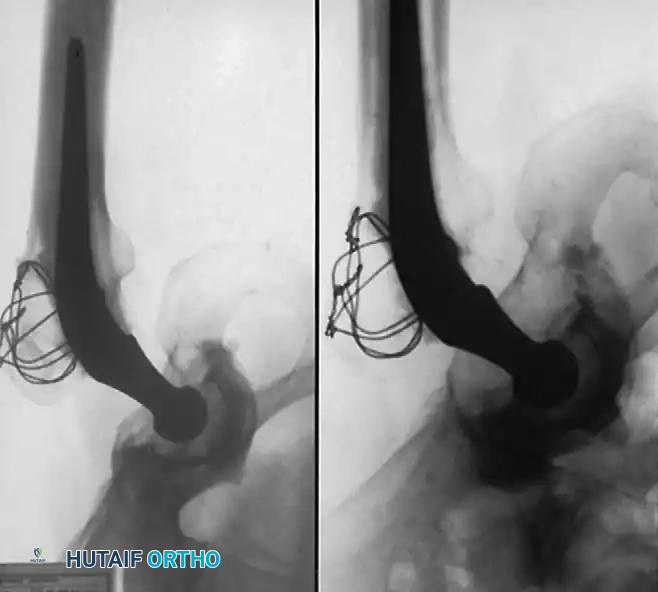

Pitfall: If the patient has previously undergone a cortical bone grafting procedure (e.g., free or vascularized fibular graft), the intramedullary portion of the graft must be completely excised. Conventional broaches will deflect off the hard cortical graft, leading to varus malpositioning and undersizing of the femoral component.

To safely remove prior grafts, the surgeon should utilize a high-speed burr and flexible reamers. Intraoperative fluoroscopy with the broach in place is highly recommended to ensure complete graft removal, proper alignment, and optimal cortical contact.

Radiographic Case Examples: Osteonecrosis and Complex Femoral Reconstructions

Advanced osteonecrosis with subchondral collapse and secondary arthritis.

Intraoperative imaging showing retained fibular graft from a previous joint-preserving procedure.

Use of a high-speed burr to clear the intramedullary canal of sclerotic graft remnants.

Fluoroscopic confirmation of proper broach alignment after graft removal.

Final seating of a cementless femoral stem in optimal neutral alignment.

Postoperative radiograph confirming excellent fit and fill of the femoral component.